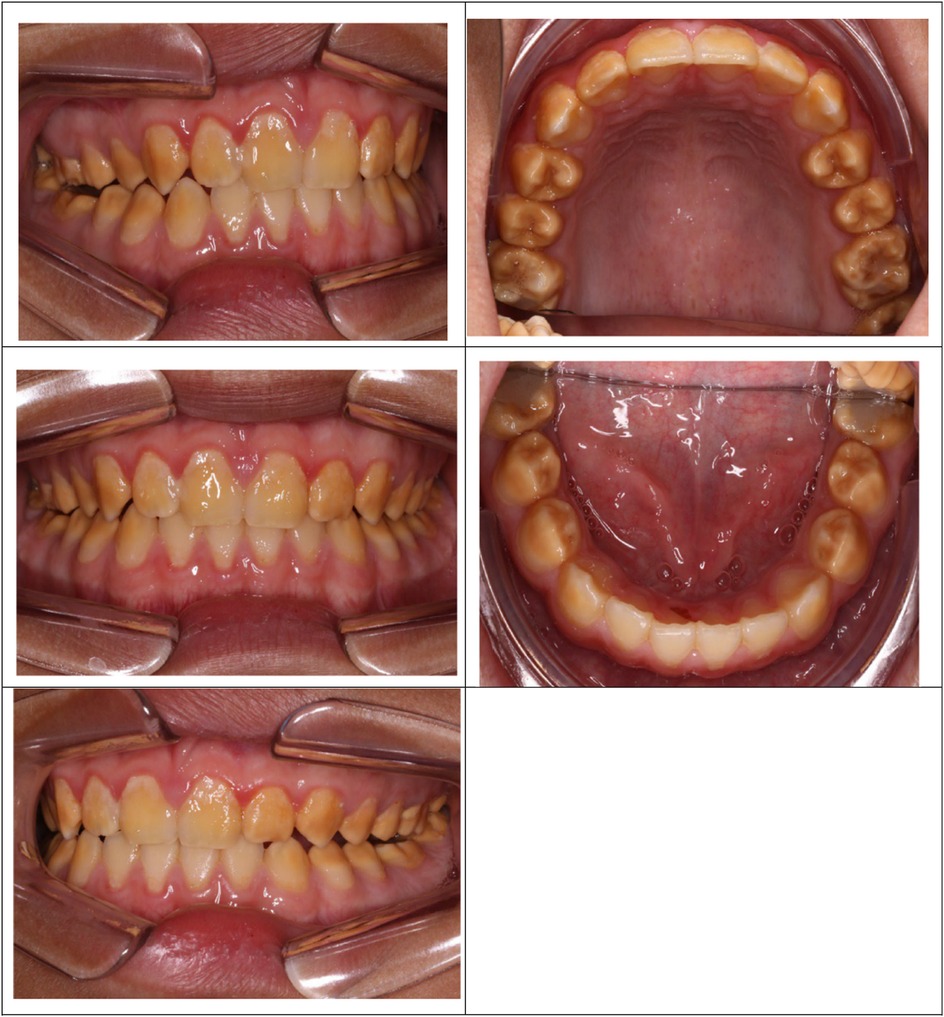

There was a mistake in Figure 2 as published. The images of the maxillary arch and mandibular arch have been positioned upside down and in the wrong order. The corrected Figure 2 appears below.

Figure 2

Figure 2. Poly AI case showing bilaterally symmetrical hypo-mineralised dentition, with mottled uniformly yellow to brown discolouration and an anterior posterior gradient in severity.